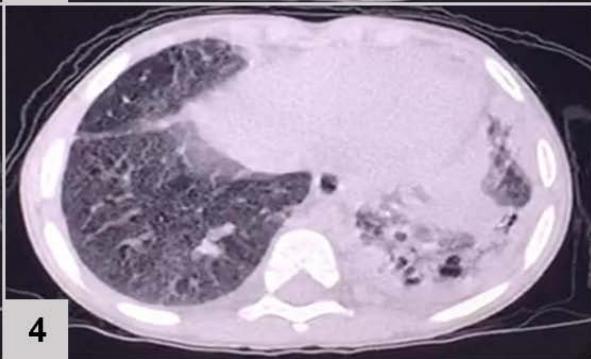

Computerized tomography (CT) of the chest (FIGURE 1)

Figure 1: CT of the chest results: extensive consolidation, with air bronchograms and cystic images in between, in the left lung (3 and 4); ground-glass opacities, diffusion in the lower left lobe (1 and 2); nodular opacity, no sign of calcification in between, on both lungs (1, 2 and 3); reticular and linear opacity and parenchymal bands in the upper lobes (3 and 4); small pleural effusion on the left (1 and 2); adjacent subsegmental atelectasis (2 and 4)

The patient's chest CT scan for the evaluation of pulmonary zygomycosis showed suggestive findings of fungal balls in both lungs, visualized as non-calcified nodular opacities and pleural effusion on the left, which is an infrequent radiological sign[^6], but of great importance for diagnosis, because the mutual presence of multiple fungal balls with pleural effusion are independent predictors of pulmonary zygomycosis[^5].